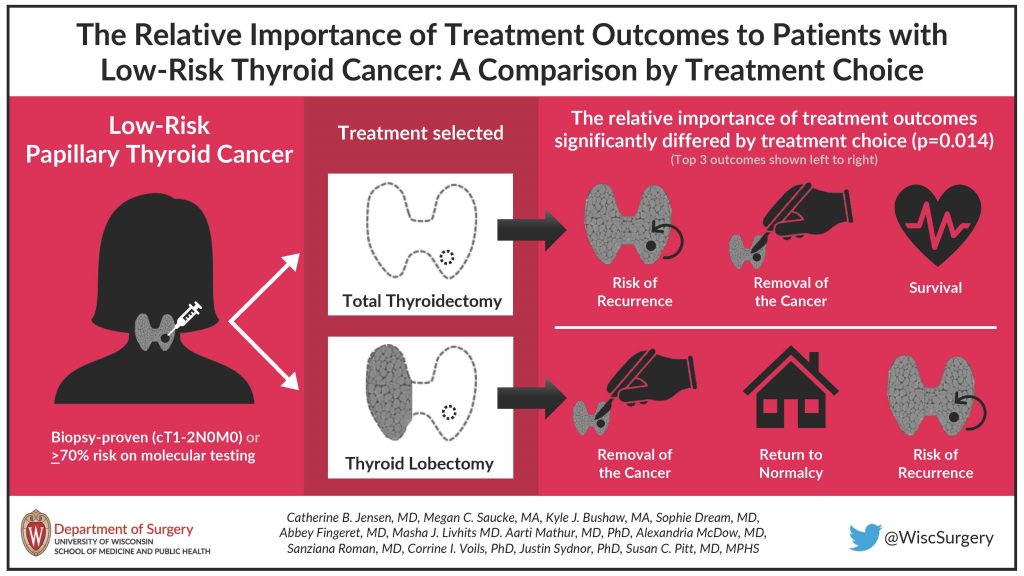

We also hold friendly competitions for the Best Surgery Science Image and the Best Visual Abstract, voted on by department members during the summit. Get a glimpse of the finalists and winners below. And for a complete overview, check out the 2023 Research Summit Program Book.

Best Visual Abstract

First Place:

Runner Up:

Runner Up: